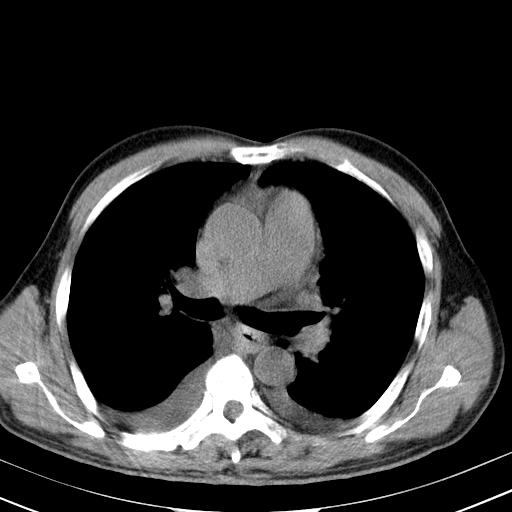

以下是引用zjzjr在2010-3-21 17:39:00的发言:[br]右下中心型肺癌并阻塞性肺炎/不张,纵膈淋巴结肿大,右侧大量胸腔积液,左侧少量胸腔积液

以下是引用zxl51642在2010-3-21 17:06:00的发言:[br]右下中心型肺癌并阻塞性肺炎/不张,纵膈淋巴结肿大,右侧大量胸腔积液,左侧少量胸腔积液,少量腹水。建议纤维支气管镜进一步检查。